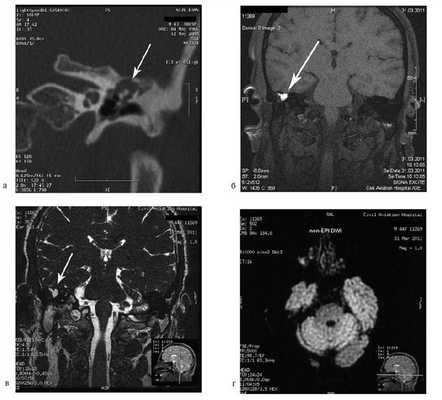

На КТ правой височной кости определяется затемнение в области аттика и антрума, цепь слуховых косточек сохранена (рис. 3, а). Рисунок 3. КТ и МРТ височных костей больного А. с адгезивным средним отитом справа, фиброзной облитерацией аттика. а — КТ; б — МРТ основания черепа в режиме Т1; в — в режиме Т2; г — в режиме non-EPI DWI.

Пациенту выполнена МРТ основания черепа по описанной методике (рис. 3, б—г).

В режиме Т1 и Т2 справа определяется очаг с высокой интенсивностью сигнала, тогда как в режиме non-EPI DWI патологических образований не выявлено. Диагноз: адгезивный средний отит справа, фиброзная облитерация аттика.

В связи с отсутствием данных о холестеатоме операция не производилась, выявленные изменения расценены как фиброзные изменения, оторея была обусловлена периодическим возникновением наружного отита. Больной получал консервативное лечение.